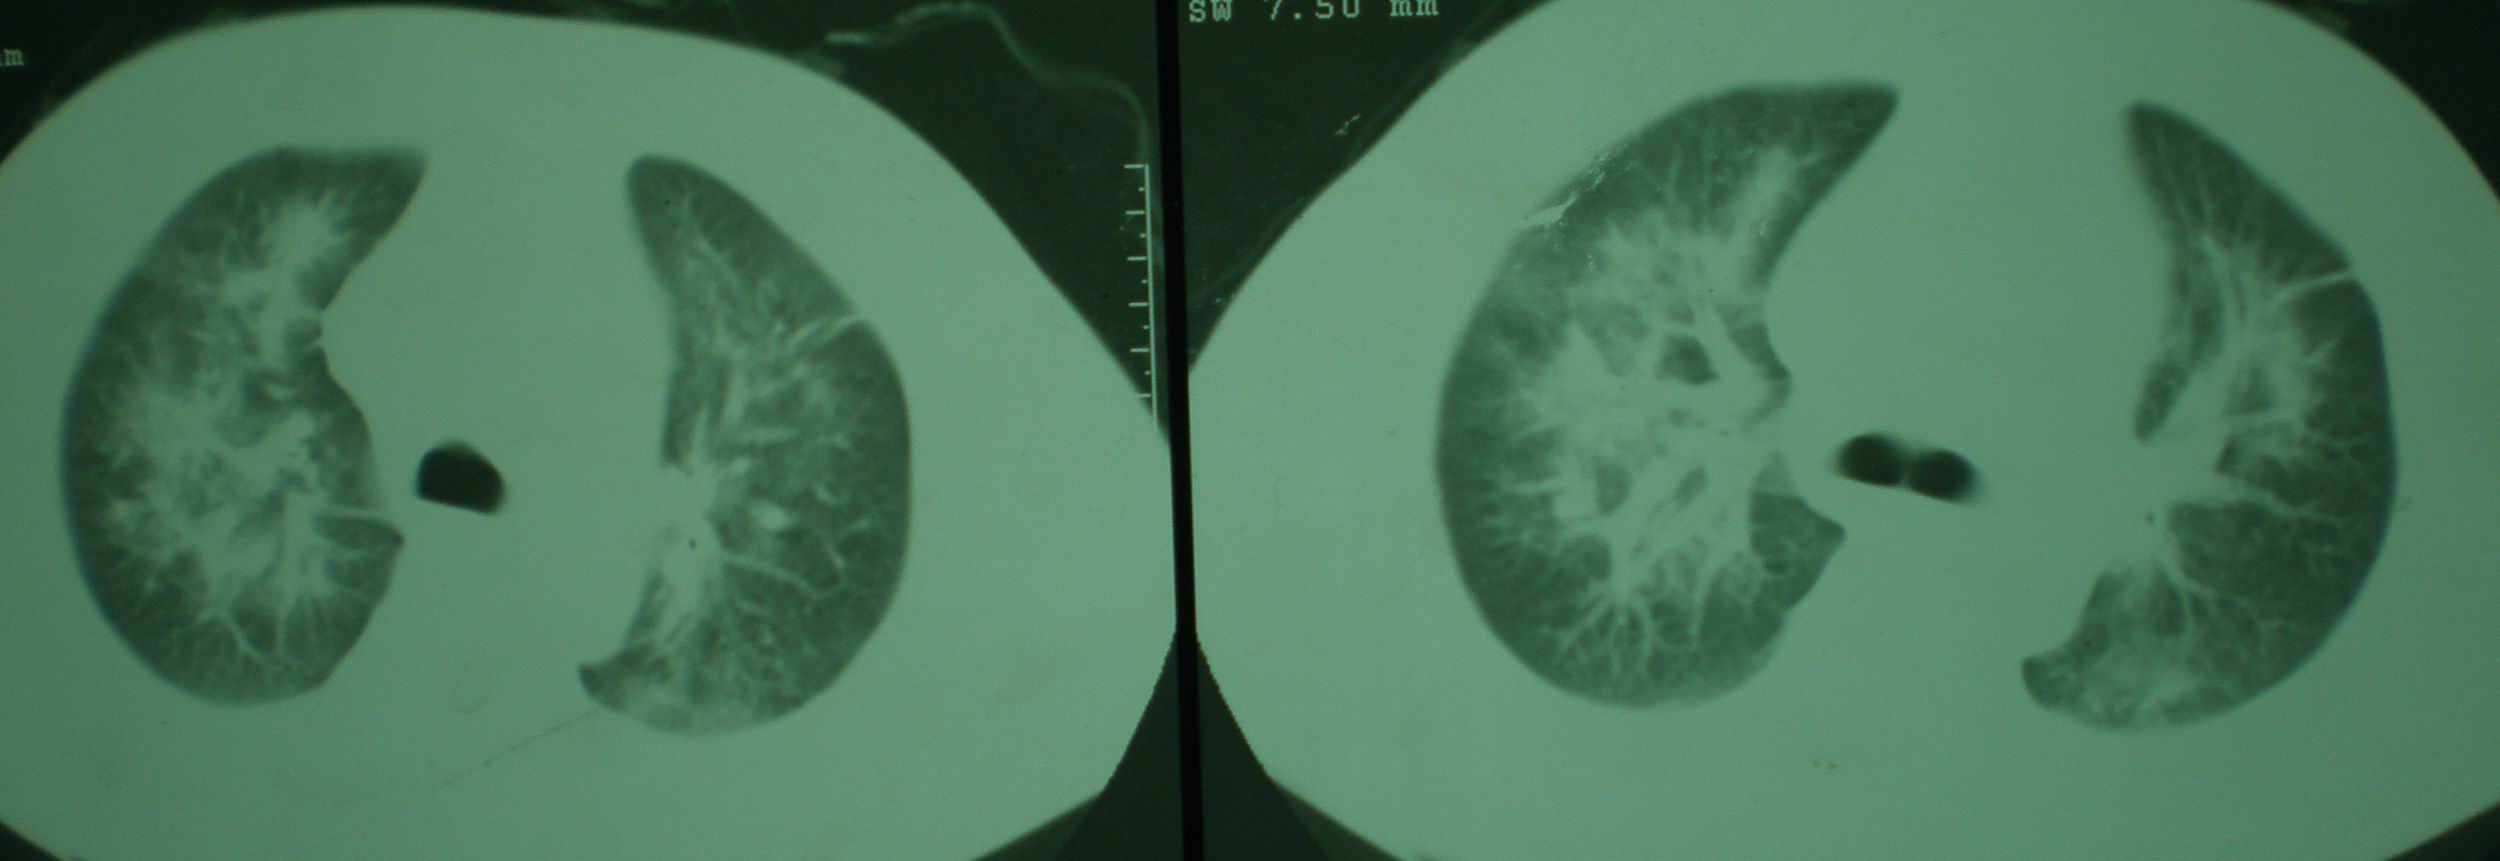

2008年11月18日今天的ct片

2008年9月18日ct片

2008年9月8日ct片: